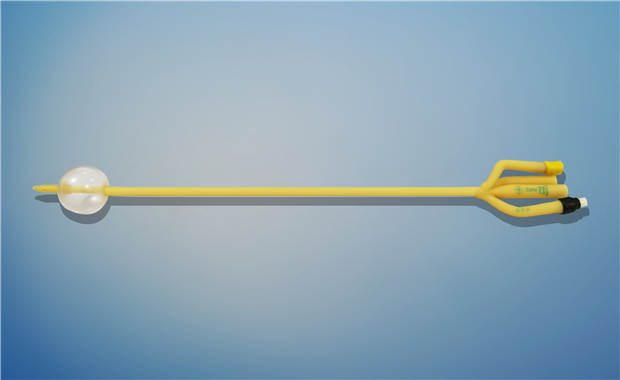

【產品名稱】一次性使用無菌導尿管(取樣型使用) 【型號】三腔氣囊取樣型 【規格】:16FR-26FR 【主要結構�、性能】由膠乳為主要原材料制成�,可配卡片。

型號:三腔氣囊標準型規格:三腔氣囊標準型:16Fr(30mL)、18Fr(30mL)���、20Fr(30mL)���、20Fr(50mL)、22Fr(30mL)���、22Fr(50mL)���、24Fr(30mL)、24Fr(50mL)�、26Fr(30mL)。結構及組成/主要組成成分:產品由導尿管����、水潤滑包(選配)組成。三腔由球囊腔充起錐...